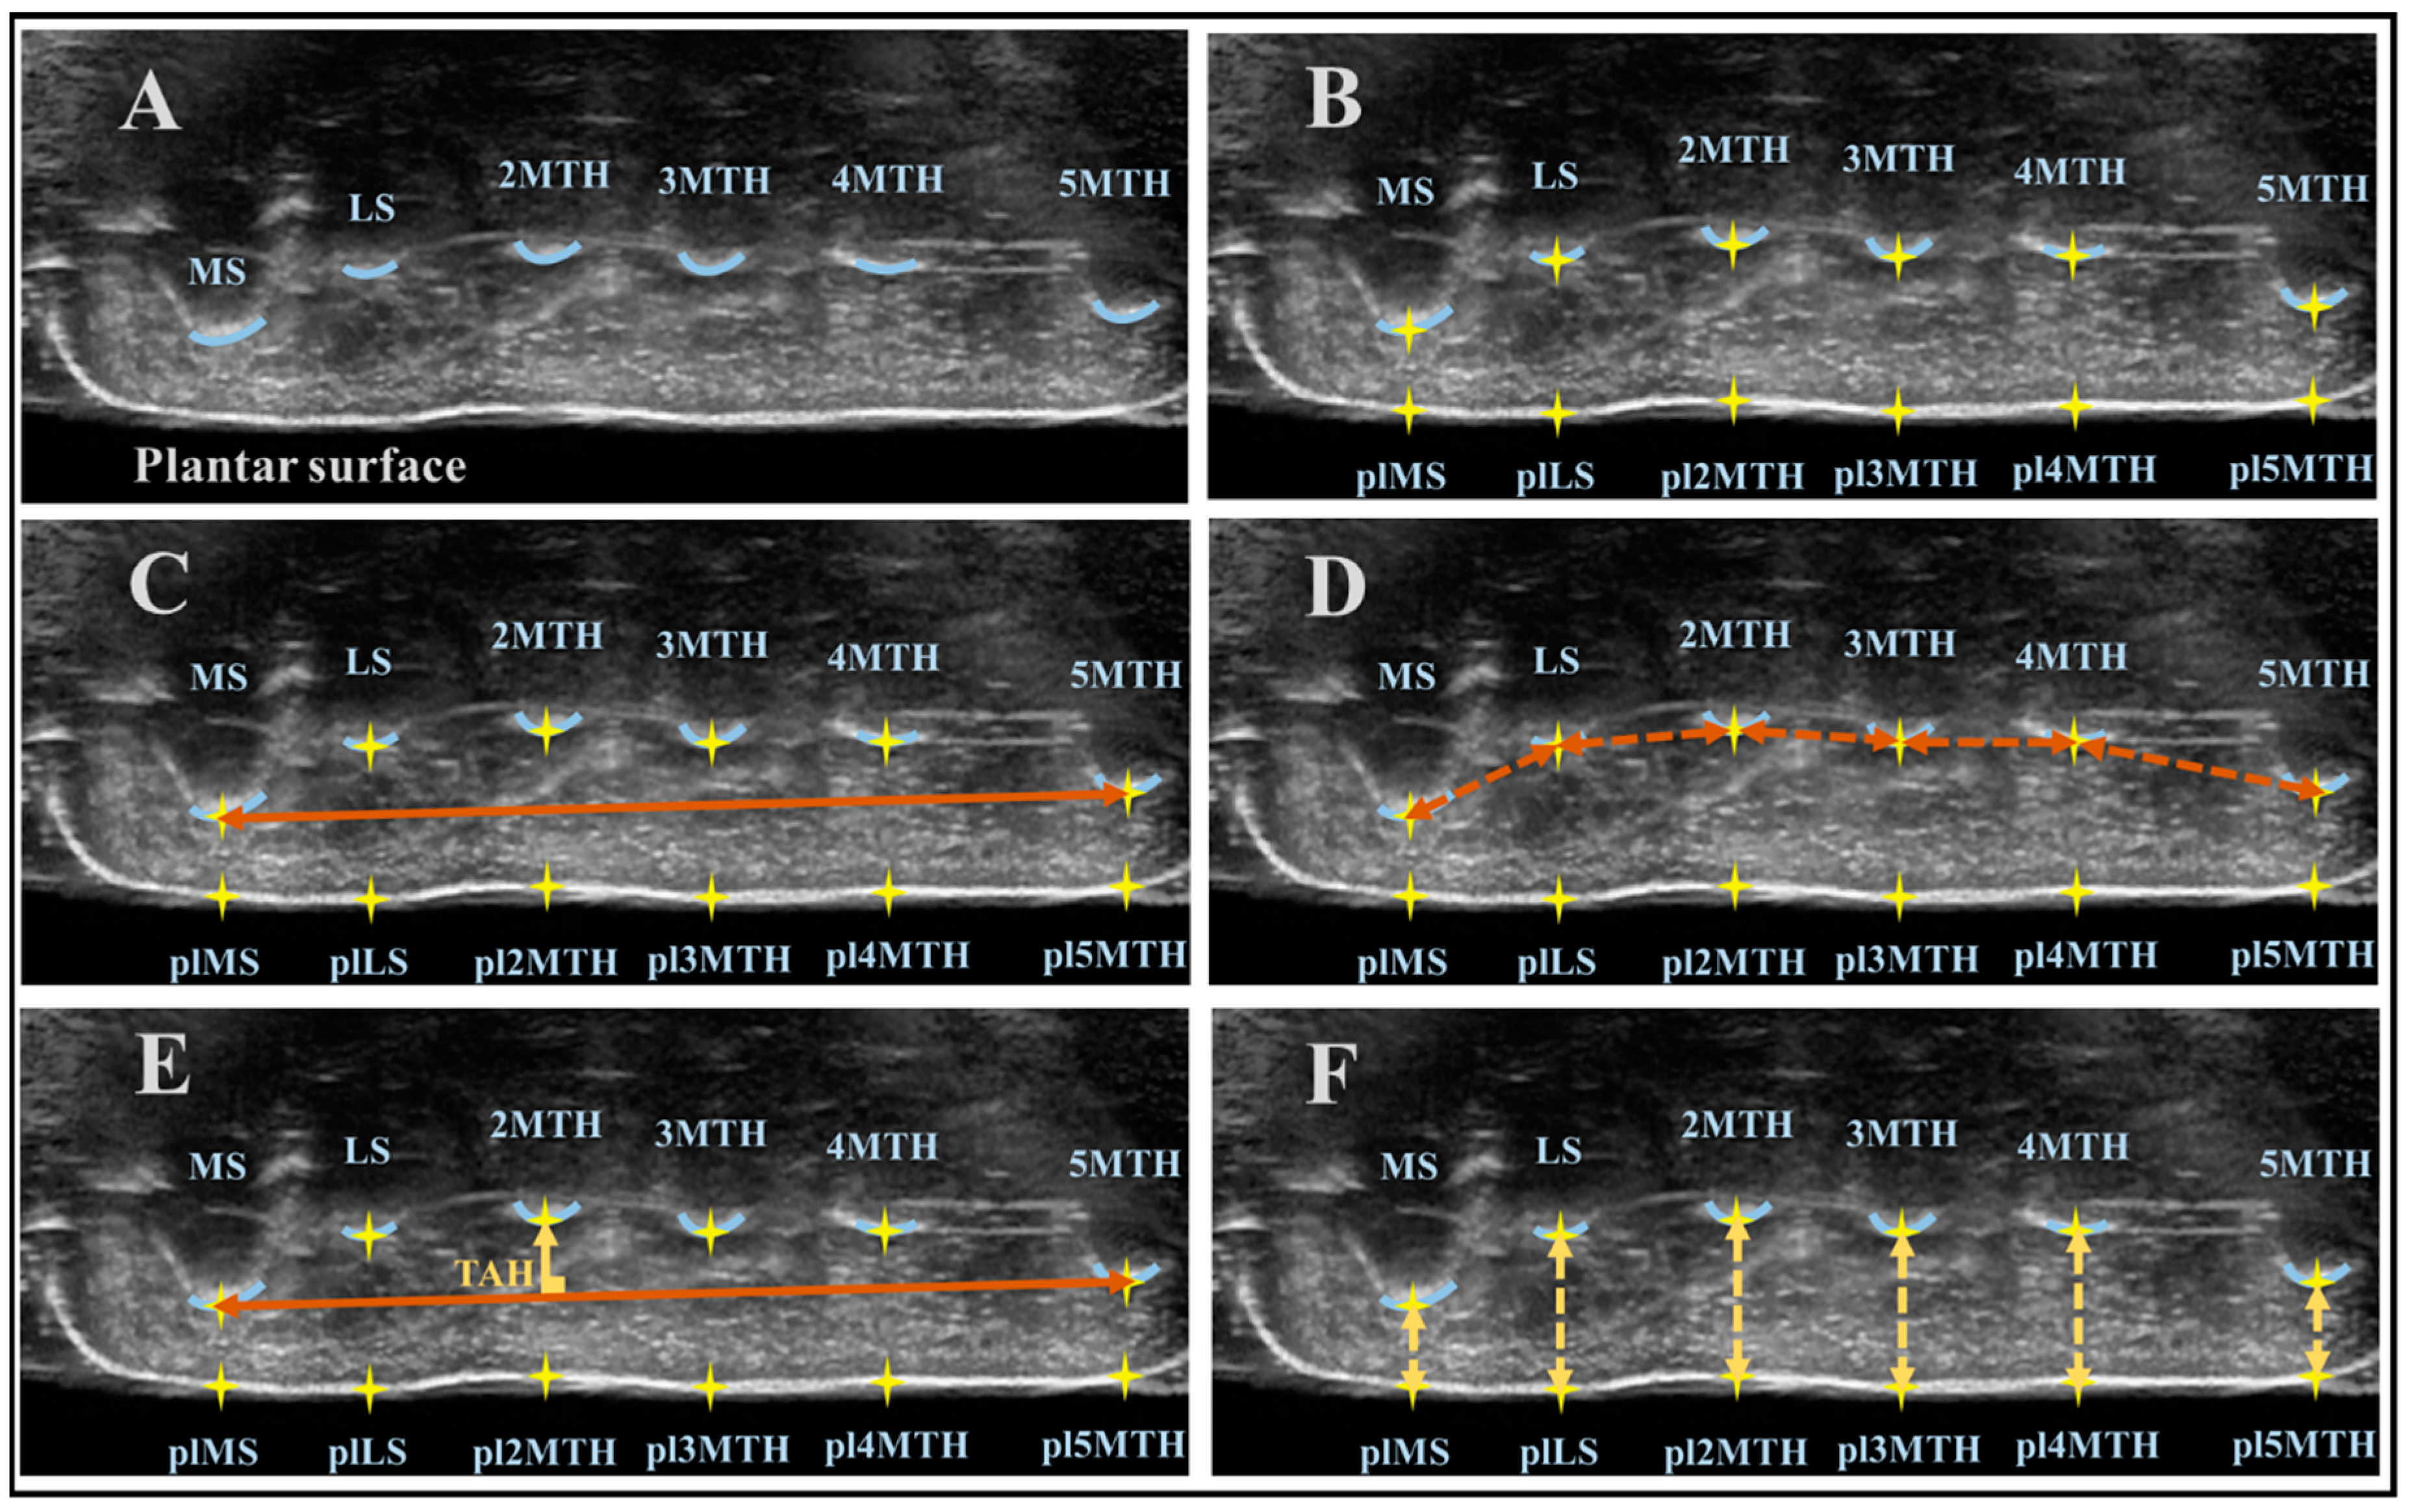

2.2. Experimental Design and Set-Up

2.3. US Data Analysis